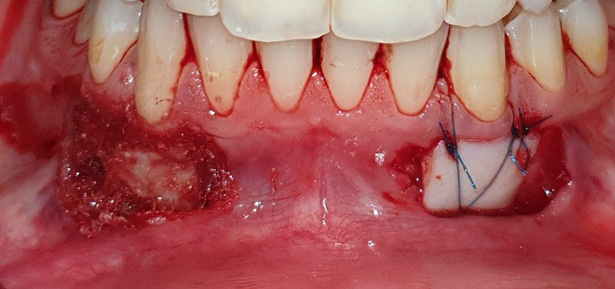

The graft was positioned in its bed and held pressed for 2 min for initial stability. At one side, the graft was stabilized using 0/5 nylon sutures (interrupted sutures to the papilla and a sling suture were placed to adapt the graft intimately to the root and periosteal bed),25 while at the other side, FGG was stabilized with the tissue adhesive (Figure 2, Figure 3, Figure 4).

As to the healing index, there were no significant differences between the 2 sites after 1 week, 2 weeks, 1 month, and 2 months. However, the healing process was completed 1 month postoperatively in the tissue adhesive group, whereas in the suture group, it lasted up to 2 months (Table 5) (Figure 5, Figure 6, Figure 7).